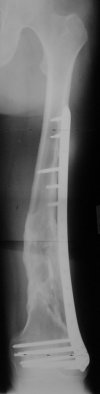

I presented a series of ~25 such cases at EuroTrauma'2004. Many cases were discussed here. I attach am example. Look also recent cases at http://www.hwbf.org/hwb/conf/alex58/scfx.htm,

http://www.hwbf.org/hwb/conf/alex63/alex63.htm

I do realize that you are master surgeon, and congratulations on another excellent, spectacular case (result), but,

- Your last posted case: how is possible to have secure fixation with applied construct without additional casting, bracing or Ilizarov?

THX, initial images are

1,

2.

At that moment we had in stock only the 10 mm solid nails so of course there was no idea about early weight bearing. But it was quite enough for early knee ROM excersises (see attached). Two locking screws through the distal block provided that.